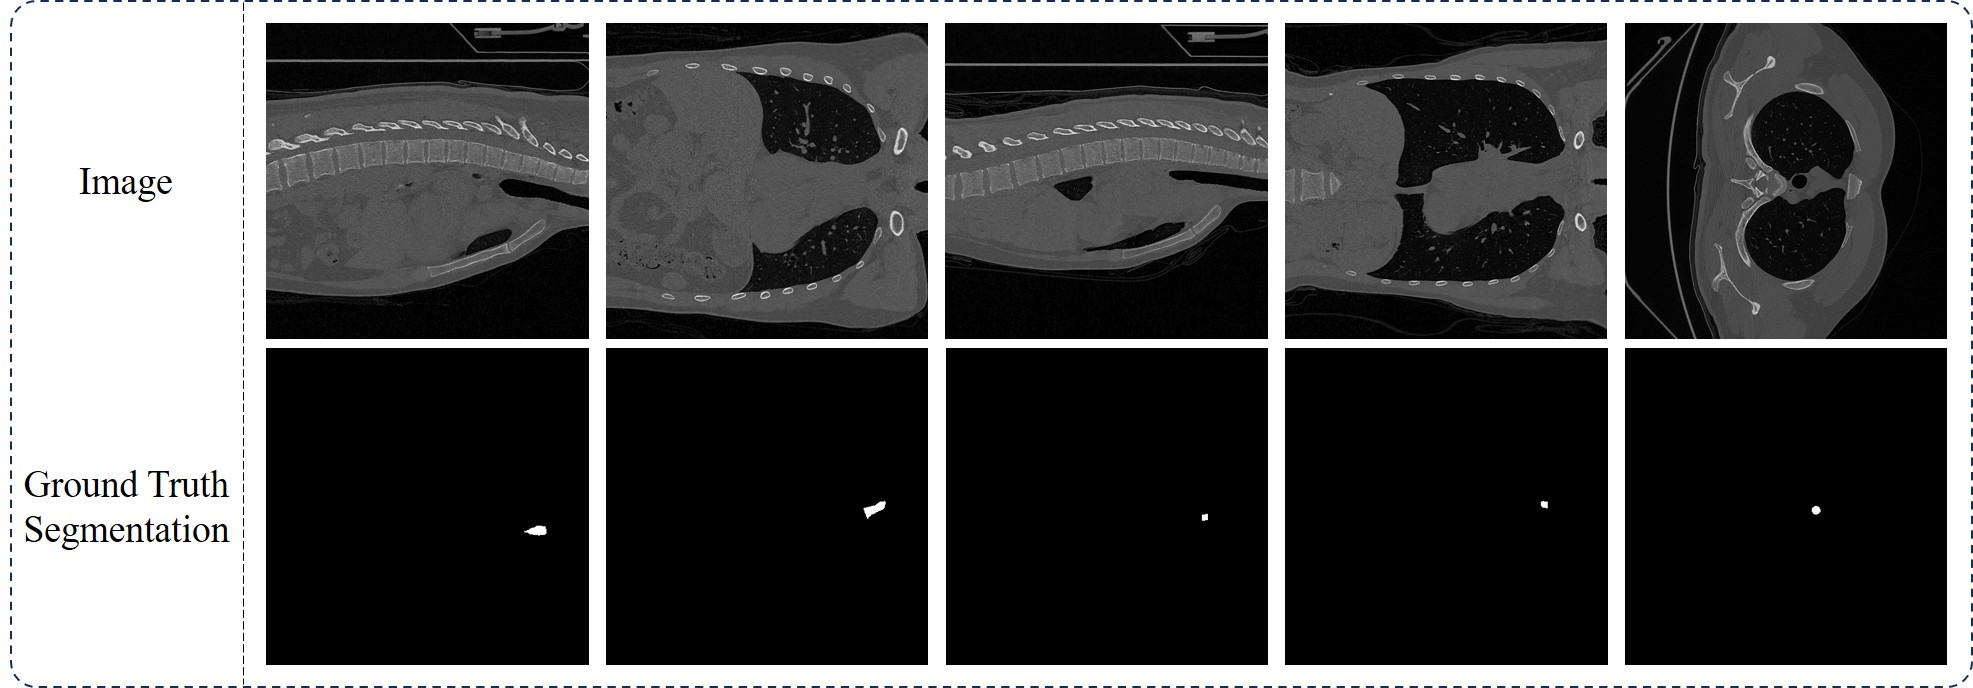

Refer to caption

Figure 2: An illustration of the training data in a scenario where bounding box was used as prompt. The regions of interest are defined by the bounding box prompts.

Pre-processing module: Given an image xisubscript𝑥𝑖x_{i}italic_x start_POSTSUBSCRIPT italic_i end_POSTSUBSCRIPT with a segmentation generated by SAM, denoted as y^i,jsubscript^𝑦𝑖𝑗\hat{y}_{i,j}over^ start_ARG italic_y end_ARG start_POSTSUBSCRIPT italic_i , italic_j end_POSTSUBSCRIPT, our objective is to combine these two elements into a single compact map. If xisubscript𝑥𝑖x_{i}italic_x start_POSTSUBSCRIPT italic_i end_POSTSUBSCRIPT is a gray-scale image, we expand its single channel to three channels; if xisubscript𝑥𝑖x_{i}italic_x start_POSTSUBSCRIPT italic_i end_POSTSUBSCRIPT is a color image (with three channels), it remains unchanged. To merge the image and the segmentation, we add y^i,jsubscript^𝑦𝑖𝑗\hat{y}_{i,j}over^ start_ARG italic_y end_ARG start_POSTSUBSCRIPT italic_i , italic_j end_POSTSUBSCRIPT to the first channel (red channel) of xisubscript𝑥𝑖x_{i}italic_x start_POSTSUBSCRIPT italic_i end_POSTSUBSCRIPT using the following formula: xi[:,:,0]=0.5×xi[:,:,0]+0.5×y^i,jsubscript𝑥𝑖::00.5subscript𝑥𝑖::00.5subscript^𝑦𝑖𝑗x_{i}[:,:,0]=0.5\times x_{i}[:,:,0]+0.5\times\hat{y}_{i,j}italic_x start_POSTSUBSCRIPT italic_i end_POSTSUBSCRIPT [ : , : , 0 ] = 0.5 × italic_x start_POSTSUBSCRIPT italic_i end_POSTSUBSCRIPT [ : , : , 0 ] + 0.5 × over^ start_ARG italic_y end_ARG start_POSTSUBSCRIPT italic_i , italic_j end_POSTSUBSCRIPT. Although there are many possible ways to combine the segmentation map and the raw image, and one could even leave this task to the following regression module (e.g., using a ResNet or ViT with more than three channels as input), we deliberately choose this simple method of combination. This approach allows us to utilize regular pre-trained vision models (e.g., ResNet, ViT) when building the regression module. After combining the maps, we use the prompt to crop the regions of interest from the full image. If the prompt is provided as a bounding box, we directly use it to crop the image within that bounding box. If the prompt is given as a center point, the cropping window is determined by y^i,jsubscript^𝑦𝑖𝑗\hat{y}_{i,j}over^ start_ARG italic_y end_ARG start_POSTSUBSCRIPT italic_i , italic_j end_POSTSUBSCRIPT111At the current stage, we focus solely on bounding-box prompts. Point-based prompts present a more challenging task, which we plan to address in the next update.. The overall pre-processing step is denoted as ψ(xi,y^i,j,pi,j)𝜓subscript𝑥𝑖subscript^𝑦𝑖𝑗subscript𝑝𝑖𝑗\psi(x_{i},\hat{y}_{i,j},p_{i,j})italic_ψ ( italic_x start_POSTSUBSCRIPT italic_i end_POSTSUBSCRIPT , over^ start_ARG italic_y end_ARG start_POSTSUBSCRIPT italic_i , italic_j end_POSTSUBSCRIPT , italic_p start_POSTSUBSCRIPT italic_i , italic_j end_POSTSUBSCRIPT ). An illustration of the data, both before and after pre-processing, is presented in Figure 2.

The 1st in-house dataset, named MRI-Kidney100, contains MRI scans from 100 individuals, designed for kidney segmentation. This dataset includes 100 3D MRI scans, from which 2D slices along the x-y plane were extracted for model testing. Similarly, the 2nd in-house dataset, named CT-BCT100, comprises CT scans from the same 100 individuals, focused on brachiocephalic trunk (BCT) segmentation. This collection includes 100 3D CT scans, with 2D slices from the x-y plane used for model testing. The 3rd in-house dataset, named Endo-Polyp1000, is a colonoscopy polyp detection dataset consisting of 1000 images, each paired with an expert-annotated mask. This dataset features a diverse range of polyp images. The 4th in-house dataset, named Path-Neuro1406, is a pancreatic neuroendocrine-related segmentation dataset with 1,406 images. In this dataset, we cropped the regions of interest from the large pathological sections stained with hematoxylin and eosin (H&E) according to doctor-annotated masks. The regions of interest vary significantly in shape and size, making segmentation particularly challenging. Image samples of these four in-house datasets can be found in Figures 345 and 6.